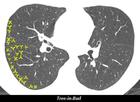

胸部X線檢查可能正常,也可能有瀰漫性間質纖維化。常出現雙側性斑塊或結節樣浸潤,支氣管肺紋理增粗,或呈小的腺泡樣改變,提示有肺水腫。肺門淋巴結腫大和胸腔積液罕見。CT特別是高分辨CT對判斷病變類型和範圍有較高價值,但CT表現無一定規律性。